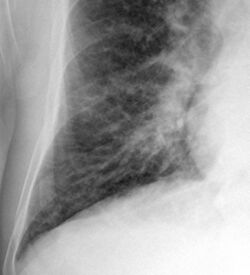

Kerley B lines in radiograph of acute cardiac decompensation. The short, horizontal lines can be found everywhere in the right lung.

Chronic stable heart failure may easily decompensate. This most commonly results from a concurrent illness (such as myocardial infarction (a heart attack) or pneumonia), abnormal heart rhythms, uncontrolled hypertension, or a person's failure to maintain a fluid restriction, diet, or medication.[50]